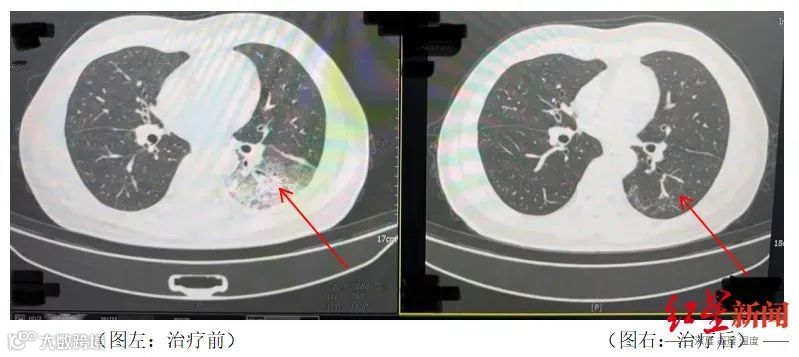

李先生的遭遇并不罕见。2024年,湖南长沙55岁市民周先生有2型糖尿病、2型糖尿病性肾病、慢性肾功能不全等多个既往史,因持续发热、寒战、咳嗽前往医院就诊。检查发现肺部存在严重感染,应用抗生素抗感染治疗后效果不佳,患者依然持续发热,还出现了神志淡漠的异常表现。

医生询问发现,周先生此前驾车出差,因为天气热,他启动了久未清洗的车载空调,每天在车上的时间超过十个小时,回来后就出现了如上症状。经过检查,最终确诊为军团菌肺炎。

周先生治疗前后的肺部CT影像